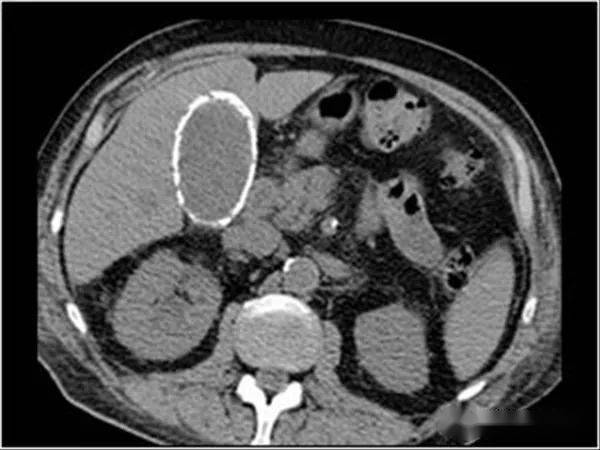

瓷化胆囊?